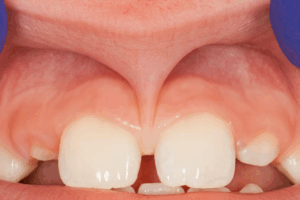

③上唇小帯と呼ばれる筋がしっかりしていて、長い

上唇小帯(上唇から上顎前歯間に付着する線維)は、付着する位置・幅・厚みが通常より、長かったり、太かったりする場合は、真ん中の隙間を物理的に引っ張ったり、介在したりして、隙間が閉じる妨げとなることがあります。

↑ 線維長くしっかりしていると隙間は埋まりません